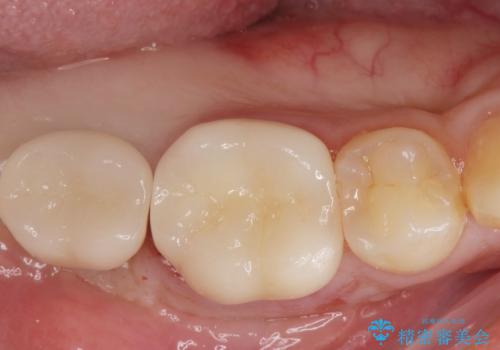

[ 失った歯の機能を回復 ] 奥歯のインプラント治療